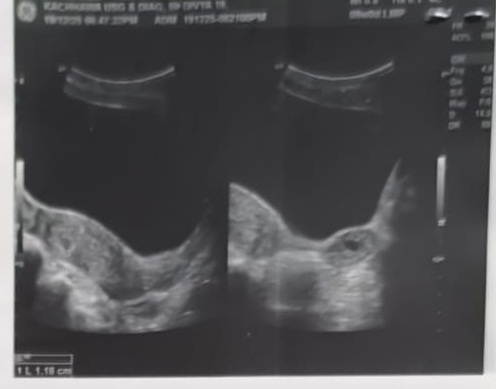

तहलका न्यूज,बीकानेर।लगातार कार्मिकों के कियाक्रलापों से विवादों में आ रही पीबीएम अस्पताल में लापरवाही का एक ओर मामला सामने आया है। जिसमें मरीज की जान पर बन आई है।मंजर यह है कि इस मामले में चिकित्सक अपनी जिम्मेदारी से बचते नजर आ रहे है। बताया जा रहा है कि 19 दिसम्बर को सुजानदेसर निवासी दिव्या गहलोत को दो माह प्रेगेन्सी के चलते रक्त स्त्राव की शिकायत के बाद जनाना अस्पताल में परिजन दिखाने ले गये।जहां डॉ संतोष खजोटिया ने सोनोग्राफी के बाद परिजनों को बताया बच्चे की धड़कन नहीं होने की वजह से प्रसूता की डीएमसी करनी पड़ेगी।परिजनों की सहमति के बाद दिव्या के ऑपरेशन कर दिया गया। एक दिन भर्ती रखने के बाद दिव्या को छुट्टी दे दी गई। लेकिन एक जनवरी को फिर से दिव्या के रक्त स्त्राव की शिकायत हुई। बाद में फिर डॉ खजोटिया को चैक करवाया गया। जांच के बाद दिव्या को घर भेज दिया गया।परिजनों के अनुसार रविवार को एक बार फिर दिव्या के रक्तस्त्राव हुआ। तो डॉ खजोटिया से स ंपर्क कर जांच की गई।जिस पर डॉ खजोटिया ने परिजनों को गर्भ में एक ओर भू्रण होने की बात कही। इस पर परिजन नाराज हो गये और शिकायत करने लगे कि पहली बार में आप को इसकी जानकारी क्यों नहीं थी।अब पन्द्रह दिनों में दोबार ऑपरेशन करना मरीज की जान पर बन जाएगा।परिजनों ने इसकी शिकायत पीबीएम अधीक्षक डॉ बी सी घीया से की तो मामला सामने आया। पता चला है कि अब चिकित्सक डॉ खजोटिया इस बात को स्वीकार नहीं कर रही है और लापरवाही को छिपाने के लिये परिजनों को दबाव बना रही है।इस घटना का जैसे ही भाजपा के पूर्व जिला उपाध्यक्ष डॉ भगवान सिंह मेड़तिया,युवा मोर्चा जिलाध्यक्ष वेद व्यास, जसराज सिंवर, विक्रम सिंह राजपुरोहित, भव्यदत्त भाटी को पता चला तो वेद व्यास,ने तुरंत इस विषय का संज्ञान लेते हुए डॉ संतोष ख़जौटियां से फोन पर वार्ता की तो डॉ के द्वारा कोई संतुष्ट प्रद जवाब नहीं दिया गया और फोन काट दिया गया।भाजपा पूर्व जिला उपाध्यक्ष डॉ भगवान सिंह मेड़तिया ने पीबीएम प्रिंसिपल डॉ सुरेन्द्र वर्मा से वार्ता की ओर कहां को 15 दिन में दो बार सर्जरी कहा तक मुमकिन है साथ ही इस विषय को गंभीरता से लेने और लापरवाही करने वाले डॉ पर अनुशासनात्मक कार्यवाही करने और मरीज को अच्छा इलाज करने को कहा।